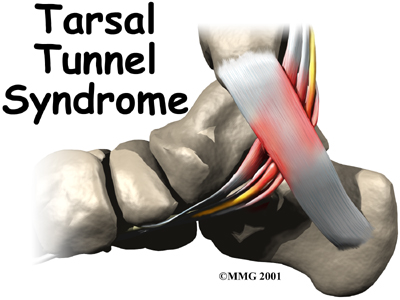

Tarsal Tunnel Syndrome

Tarsal tunnel syndrome is a condition that occurs from abnormal pressure on a nerve in the foot. The condition is similar to carpal tunnel syndrome in the wrist. The condition is somewhat uncommon and can be difficult to diagnose.